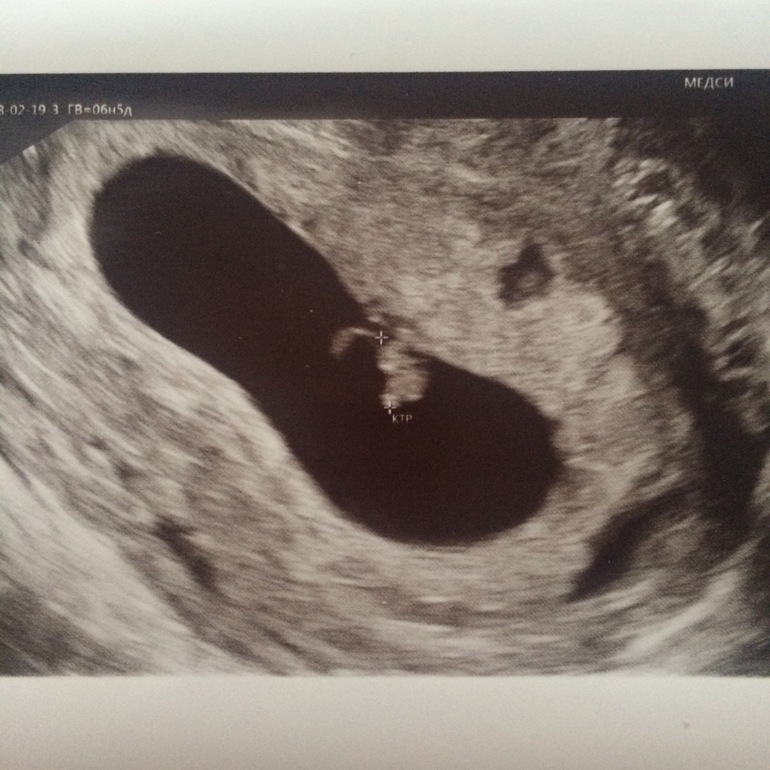

Год назад узнала, что у меня будет маленькая бусинка. Но не представляла, какая хорошенькая и любимая и ей уже 3,5 мес. Помню мужу купила конфеты ручной работы и внутри на картоне нарисовала три сердечка )) реакция, конечно, была не однозначная-мужская паника) А сейчас папина дочка растёт и радует нас всех